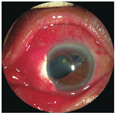

患者男,57岁。2014年1月于河南省立眼科医院就诊,1个月前,自觉左眼异物感,视力下降,并发现左眼泡样隆起物,来我院就诊。追问病史,患者30年前左眼曾被扫帚击伤,未行手术治疗,全身及局部应用药物治疗,视力稍有下降。本次入院检查:视力:右眼0.8,左眼0.1;眼压:右眼16 mmHg,左眼15 mmHg。左眼鼻下方球结膜可见巨大泡样隆起,壁薄,6点至9点位角巩膜缘处可见巩膜葡萄肿,余角膜透明,前房中深,瞳孔呈梨形,向鼻下方移位明显(图1)。左眼UBM检查角膜回声清晰,中央前房深2.4 mm,瞳孔向鼻侧移位,8点位角巩膜缘处连续性中断,断口直径约0.57 mm,缺损处上方少部分向前房内弯曲,对应处见巨大结膜滤过泡,与前房沟通,呈分叶状(图4)。左眼B超见玻璃体混浊。根据患者外伤史及检查所见,诊断为:左眼前巩膜葡萄肿伴巨大滤过泡,入院行异体巩膜移植术。手术方法:因滤过泡与前房沟通,为避免切开滤过泡时眼压骤降,先行前房穿刺,降低眼压,沿角膜缘剪开鼻下方球结膜,暴露巩膜葡萄肿,发现8点处角巩膜缘穿孔,虹膜嵌顿,与周围组织粘连较重,去除虹膜表面结膜上皮,回纳部分虹膜,板层剖切穿孔周围巩膜,取相应大小异体巩膜植片间断缝合于巩膜植床。术后第3天:球结膜充血水肿,角膜透明,前房中深,瞳孔不规则,直径约4 mm(图2)。复查UBM见左眼角膜回声清晰,中央前房深2.6 mm,角巩膜未探及低回声区(图5)。术后取剖切巩膜病理检查示:巩膜穿孔,可见虹膜组织粘连,符合葡萄肿改变(图3)。